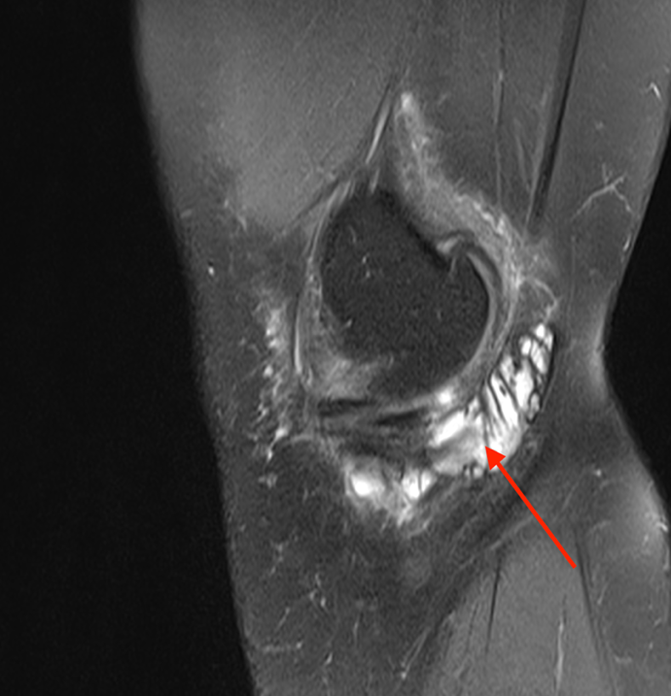

MRI jest złotym standardem w różnicowaniu zespołu zapalenie gęsiej stopki od innych wewnątrzstawowych i pozastawowych patologii kolana6. Charakterystyczne cechy obrazu MRI to:

- Płyn w kaletce pes anserinus – hipointensywny w T1, hiperintensywny w T2 Zdjęcie 2.

- Zlokalizowany poniżej ścięgien pes anserinus, na wysokości górnego końca kości piszczelowej

- Często współistnienie zmian zwyrodnieniowych w stawie kolanowym

- Możliwość wykrycia obrzęku tkanek miękkich i szpiku kostnego

Należy pamiętać, że obecność płynu w kaletce u 5% osób bezobjawowych oznacza, że rozpoznanie zespołu zapalenie ścięgien gęsiej nie może opierać się wyłącznie na obrazie MRI – konieczna jest korelacja z objawami klinicznymi 3,6.

Zdjęcie 2. Obrazy rezonansu magnetycznego, czerwona strzałka wskazuje obecność płynu wokół ścięgien, co sugeruje zapalenie.